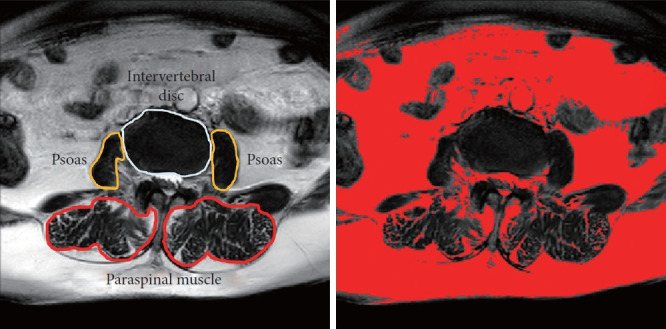

Methods: One hundred thirty-eight patients with DK and 204 with lumbar spinal stenosis (LSS) were enrolled. The spinopelvic parameters and sagittal vertical axis (SVA) were measured. Patients were divided into the sagittal balance (SB, SVA ≤ 5 cm, n = 61) and SI (SVA > 5 cm, n = 77) groups. Sagittal balanced LSS patients were served as control group. PSM function was evaluated by measuring the maximal voluntary exertion (MVE) and endurance time (ET). Magnetic resonance imaging-derived cross-sectional area (CSA) and fat infiltration rate (FI%) of PSM at T10-L5 were normalized to intervertebral disc CSA. Psoas CSA and FI% were calculated at L3-4 disc level. The correlation assessment using Spearman rank correlation coefficient and multiple linear regression. Logistic regression was used to identify the risk factors of SI.